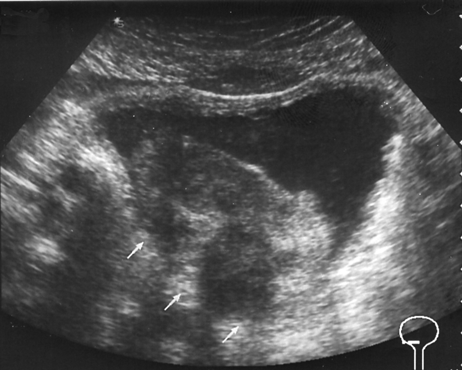

Рисунок 1. Рак мочевого пузыря, стадия T3b

УЗТ мочевого пузыря в поперечной плоскости. Опухоль располагается на правой боковой и задней стенках. Стрелками указана зона инфильтрации околопузырной клетчатки